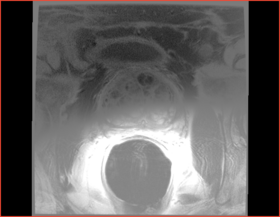

Prostate erMRI

After bias correction